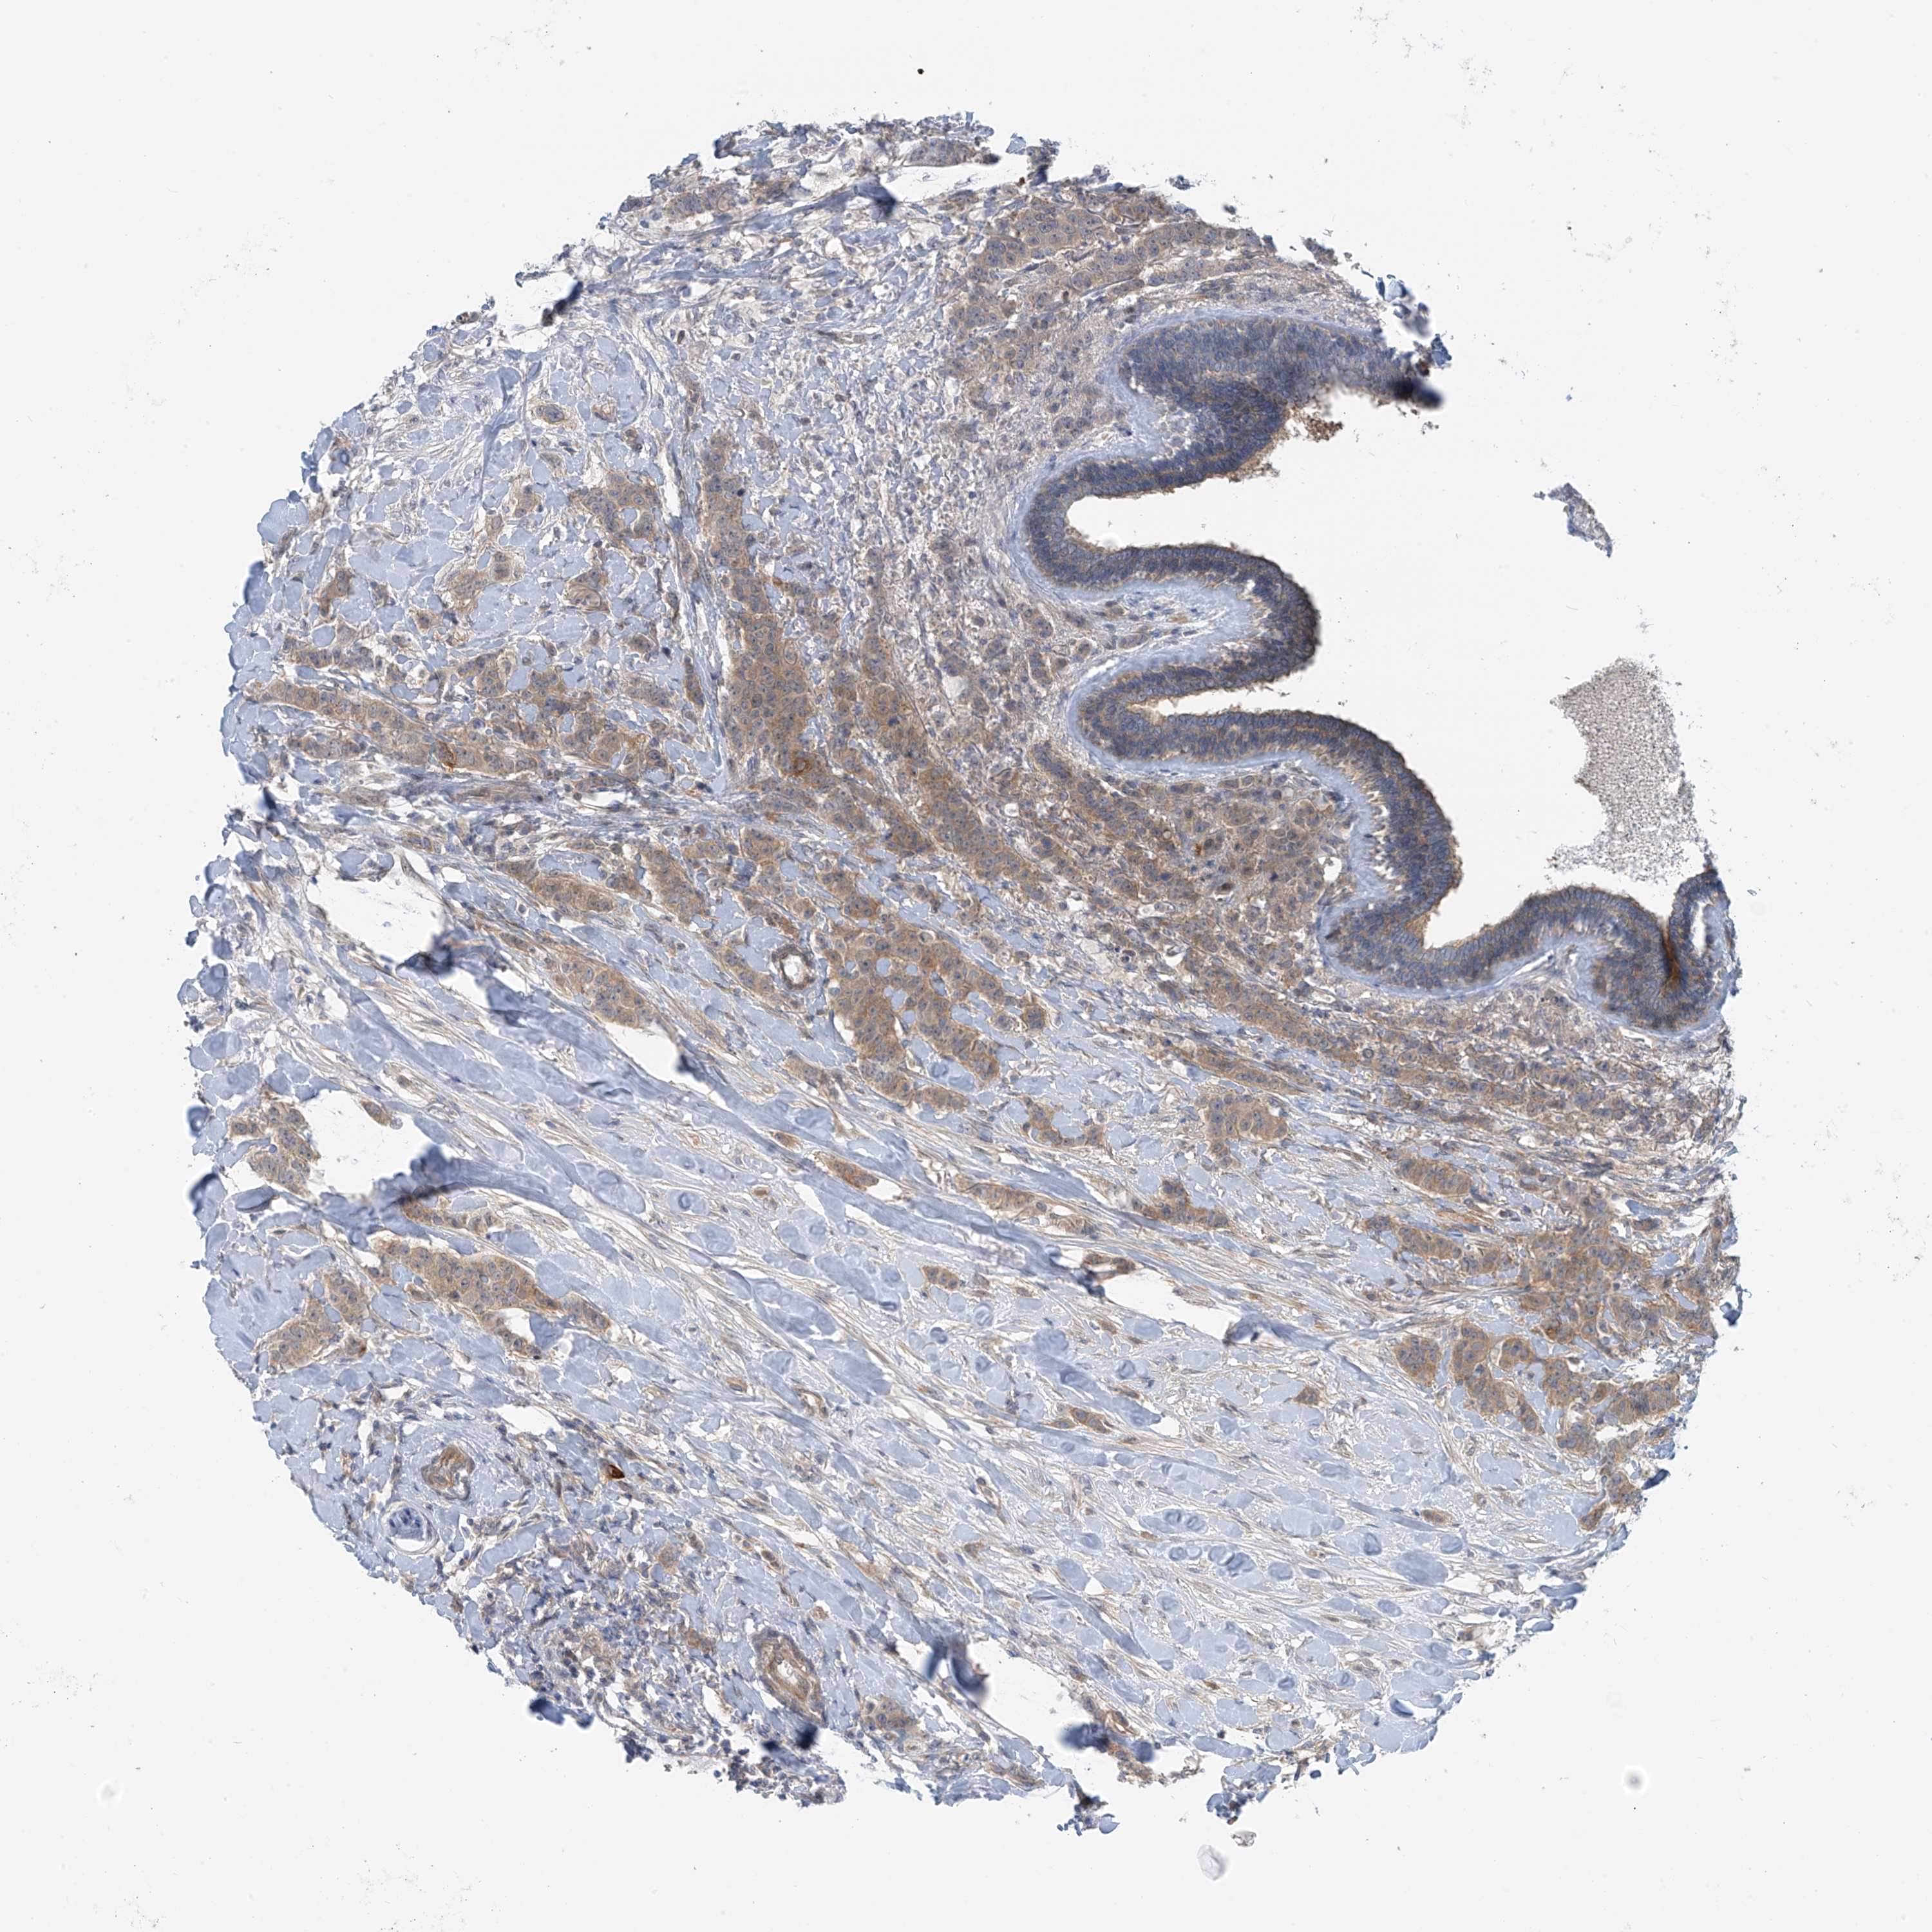

CANCER BREAST CANCER Show tissue menu

BRCA TCGA BRCA VALIDATION PROTEIN EXPRESSION